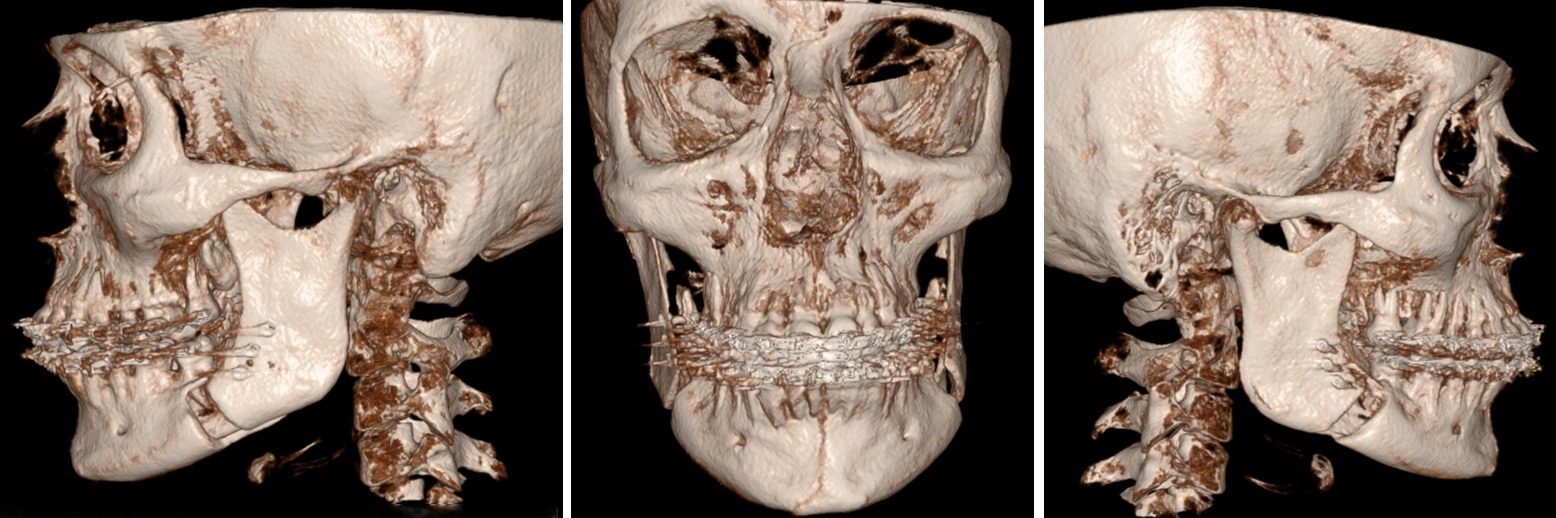

Röntgen beeld na operatie